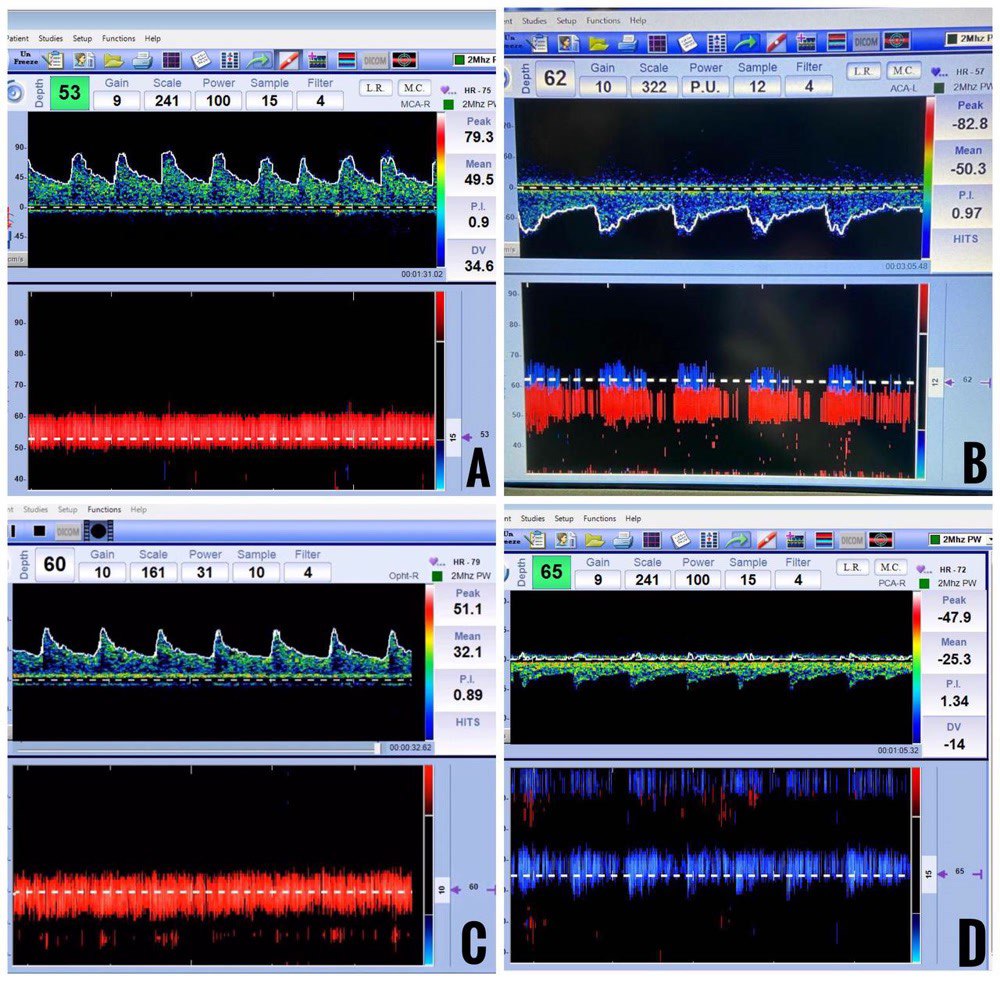

A = middle cerebral artery, B = anterior cerebral artery, C = posterior cerebral artery (P1 segment), and D = posterior cerebral artery (P2 segment).

A = ophthalmic artery, B = carotid siphon

A = vertebral artery, B = basilar artery

Figure 7: Spectral waveforms of arteries insonated at the submandibular window.

A = external carotid artery, B = internal carotid artery

A low-frequency (2 MHz) transducer with a circular footprint insonates cerebral vessels at insonation windows. Transtemporal, suboccipital, submandibular, and transorbital windows are the four standard insonation windows utilized during TCD examination (Figure 3). Each insonation window is unique, allowing us to insonate and examine specific cerebral blood vessels (Figures 4-7). Techniques to insonate and identify cerebral blood vessels through the four standard insonation windows are summarized in Table 2.3

| Transtemporal | The patient is supine with the head in a neutral position. The transducer is placed on the temporal aspect of the skull, cephalad to the zygomatic arch and anterior to the tragus. The probe's anterior angulation will help in better localizing ACA. | MCA | 30-65 | Towards | 55 ± 13 |

| ACA | 60-75 | Away | 50 ± 11 | ||

| Slight inferior angulation of the transducer from the position as mentioned above. | ICA Bifurcation | 51-65 | Bidirectional | 39 ± 9 | |

| Slight posterior angulation of the transducer from the position as mentioned above for MCA. | P1 segment of PCA | 55-75 | Towards | 39 ± 10 | |

| P2 segment of PCA | 55-75 | Away | 40 ± 10 | ||

| Transorbital | The patient is supine with the head in a neutral position. The transducer is placed on the orbit and angulated in inferior and medial directions. | OA | 40-50 | Towards | 21 ± 5 |

| Same as mentioned above for OA. | CS | 58-65 | Variable | 41 ± 11 | |

| Suboccipital | The patient is in a lateral decubitus position with the head slightly flexed. The transducer is placed on the nuchal crest slightly off the midline and angulated in superior and medial directions. | VA | 40-75 | Away | 37 ± 10 |

| Slight superior angulation of the transducer from the position as mentioned above. | BA | 80-105 | Away | 41 ± 10 | |

| Submandibular | The patient is supine with the head in slight extension. The transducer is placed below the angle of the mandible and angulated in superior and medial directions. | Extracranial ICA | 35-80 | Away | 34 ± 9 |